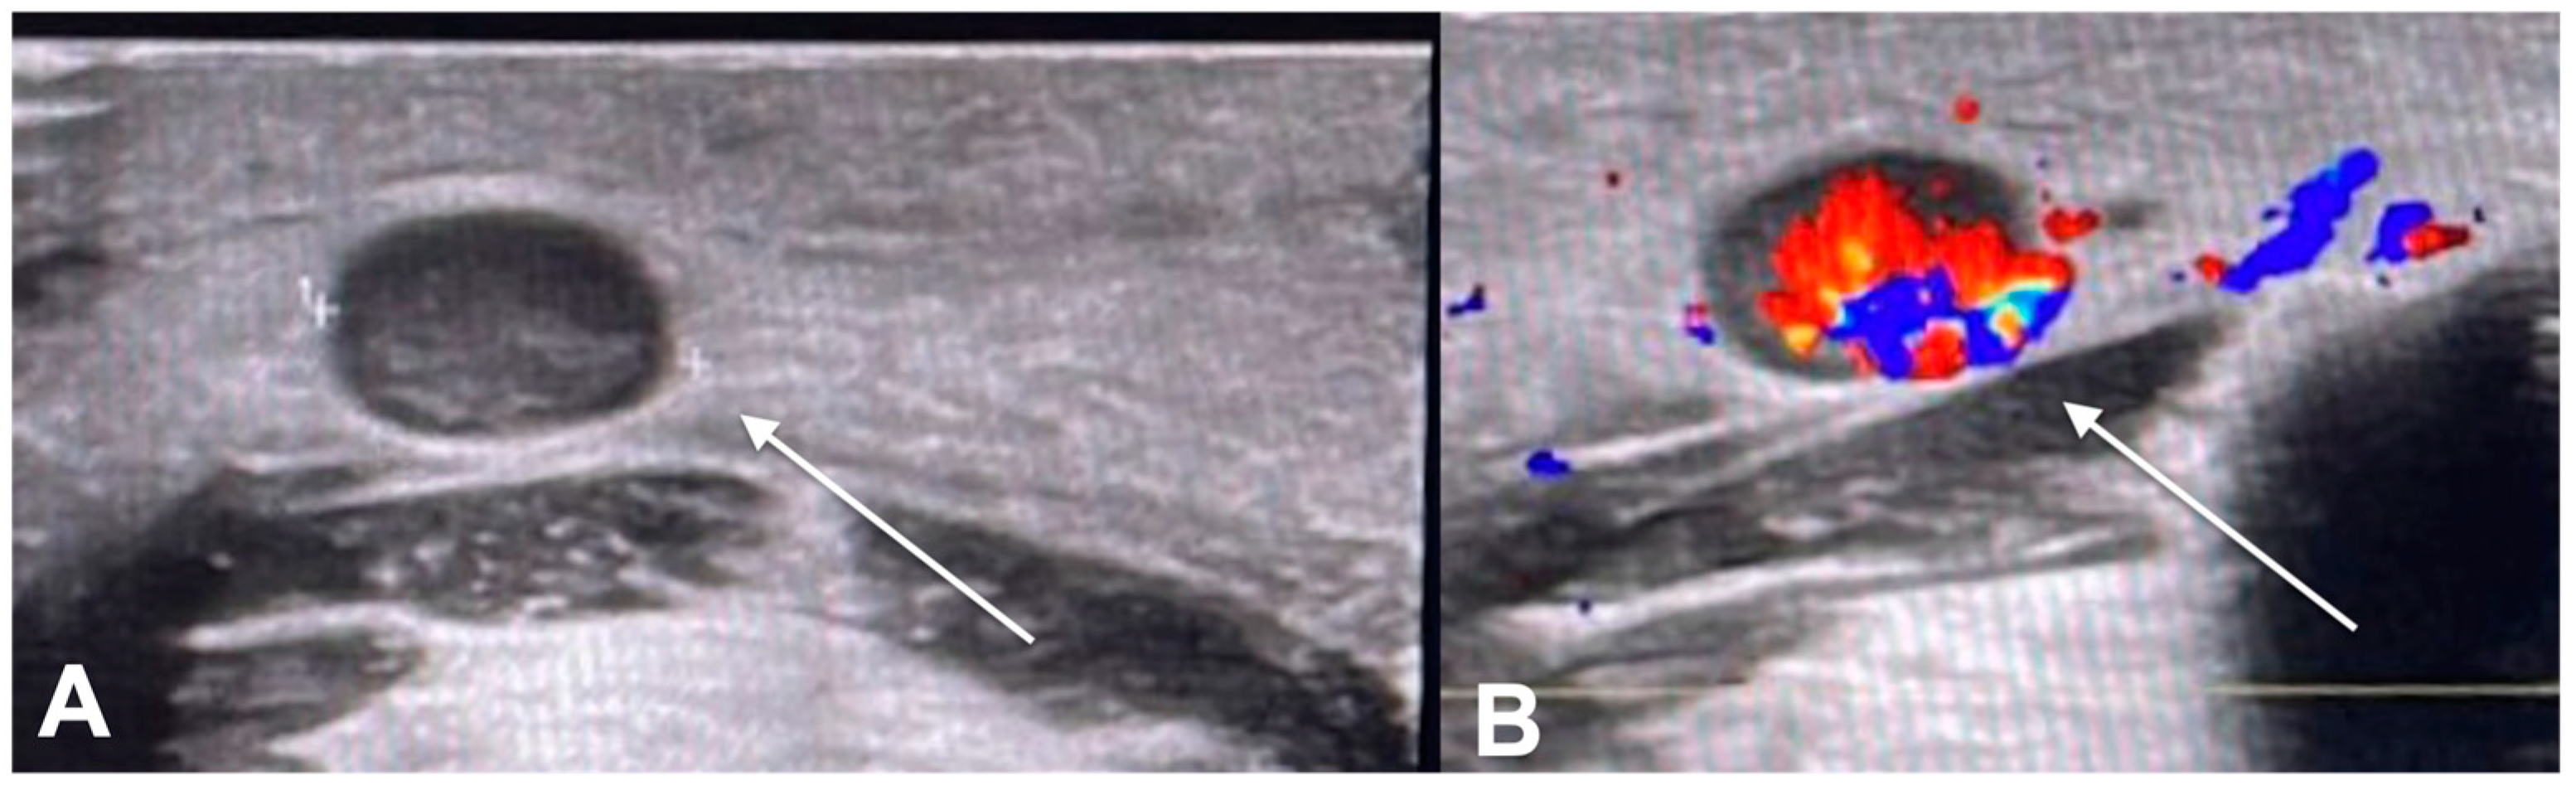

- Catalano, O.; Roldán, F.A.; Varelli, C.; Bard, R.; Corvino, A.; Wortsman, X. Skin cancer: Findings and role of high-resolution ultrasound. J. Ultrasound 2019, 22, 423–431. [Google Scholar] [CrossRef] [PubMed]

- Crisan, M.; Crisan, D.; Sannino, G.; Lupsor, M.; Badea, R.; Amzica, F.; Lupsor-Platon, M. Ultrasonographic staging of cutaneous malignant tumors: An ultrasonographic depth index. Arch. Dermatol. Res. 2013, 305, 305–313. [Google Scholar] [CrossRef]

- Wortsman, X.; Wortsman, J. Clinical usefulness of variable-frequency ultrasound in localized lesions of the skin. J. Am. Acad. Dermatol. 2010, 62, 247–256. [Google Scholar] [CrossRef] [PubMed]

- Wang, S.-Q.; Liu, J.; Zhu, Q.-L.; Zhao, C.-Y.; Qu, T.; Li, F.; Wortsman, X.; Jin, H.-Z. High-frequency ultrasound features of basal cell carcinoma and its association with histological recurrence risk. Chin. Med. J. 2019, 132, 2021–2026. [Google Scholar] [CrossRef]

- Dinnes, J.; Bamber, J.; Chuchu, N.; Bayliss, S.E.; Takwoingi, Y.; Davenport, C.; Godfrey, K.; O’Sullivan, C.; Matin, R.N.; Deeks, J.J.; et al. High-frequency ultrasound for diagnosing skin cancer in adults. Cochrane Database Syst. Rev. 2018, 2018, CD013188. [Google Scholar] [CrossRef]